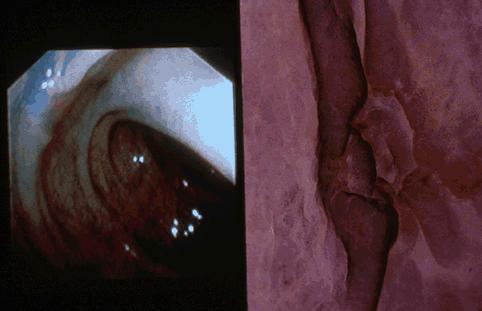

Type 0-IIc (superficial depressed type) early colon cancer showing lateral, frontal and oblique images of the lesion.

Malignant epithelial tumor/Adenocarcinoma

Large intestine(Colon)/Descending colon

Endoscopy

Type 0/IIc (IIc) Superficial depressed type

1 - 9

mucosa